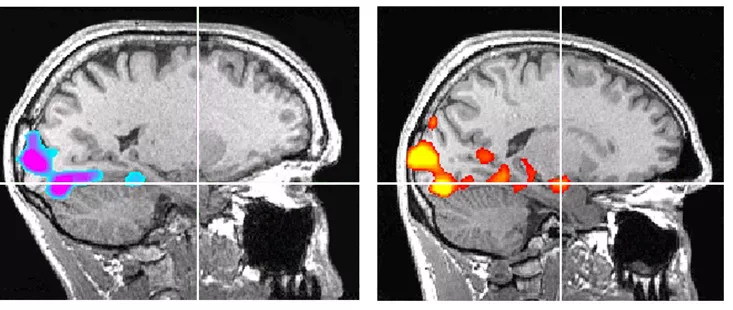

If the reports are to be believed, in 2016, Alex Honnold had his brain checked by the University of South Carolina. The test was conducted to see how his brain reacts to fear, or whether it works differently from other people's, as Alex often chooses to climb without ropes or safety gear. If a report by fMRI is to be believed, he has an underactive amygdala.

The amygdala is a key part of the brain that registers fear, and when there's any sign, it makes the body feel scared or stressed. In Alex's case, the test was to find out whether his amygdala is quieter or handled differently. After the test, cognitive neuroscientist Jane Joseph said that maybe his amygdala isn't firing, or that he has a well-honed regulatory system, and along with that, he also has a powerful frontal cortex that calms him down. Jane Joseph, back then, said:

"Maybe his amygdala is not firing—he’s having no internal reactions to these stimuli. But it could be the case that he has such a well-honed regulatory system that he can say, ‘OK, I’m feeling all this stuff, my amygdala is going off,’ but his frontal cortex is just so powerful that it can calm him down.”